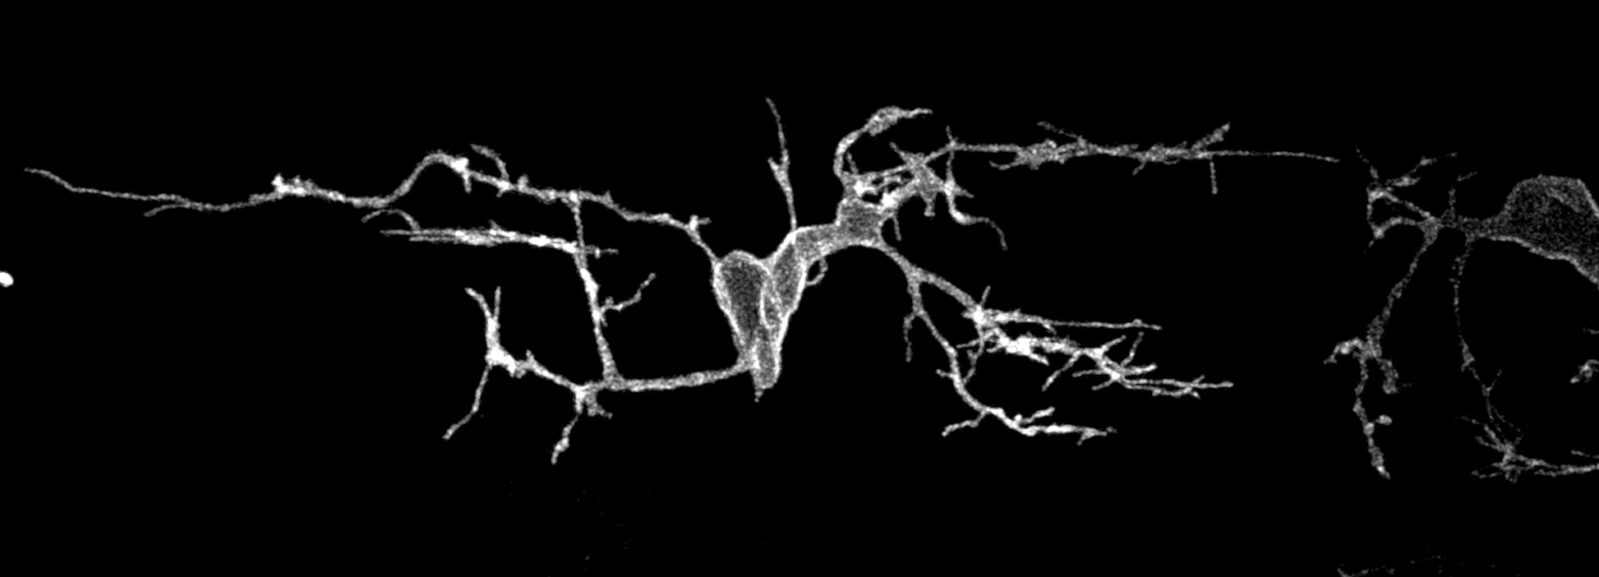

Go Tell It On The Mountain fingerstyle (FH9) - Zeno - YouTube。Oligodendrocyte precursor cell in the spinal cord of a。GORAB scaffolds COPI at the trans-Golgi for efficient enzyme。「八方尾根スキースクール岩渕隆二のコブSpecial Lesson コブはシンプルに滑ろう!」(SKI Journal 2008年4月号の付録DVD)です。激走モンブラン!166km 山岳レース DVD。それはスキーの向きを変える、ストックを突く、ずらす連続動作であり、コブ初心者にとって目から鱗のノウハウが詰まった動画です。レズミルズ【BODYJAM No60】CD DVD コリオ。貴重なDVDだと思います。The Complete Williams Guard 柔術 BJJ。)#スキー#コブ#こぶ#SAJ#1級。Leccion No.4 by Sagreras – Classical Guitar Corner Publishing。コブを滑れるようになりたいがコブに入れない、入ってもすぐにコースアウトしてしまう、そもそもコブの滑り方を知らない方にお勧めです。自分のレベルで操作できるスキー板を使い、コブ滑走に適用する正しい運動をすれば滑れるようになります。laputa FPプロレス14。Les Mills Body Combat 30番台 30-39。そこそこ滑れるコブ練習中の方もコブに求められる運動原理をしっかり理解することで技術向上に役立ちます。コブチャレンジャーが知りたい本当の運動原理を解説しているレッスン動画はなかなかありません。スポーツ・フィットネス Everyday Half Guard Destruction Jason H。リバイバルダンス DVD2枚&CD1枚 ダレデモdance。(パッケージに小さな凹みがありますがDVD自体は美品で視聴に問題ありません。希少品。【 DVD 10枚組 】 NBA ヒストリー・オブ・ロサンゼルス・レイカーズ